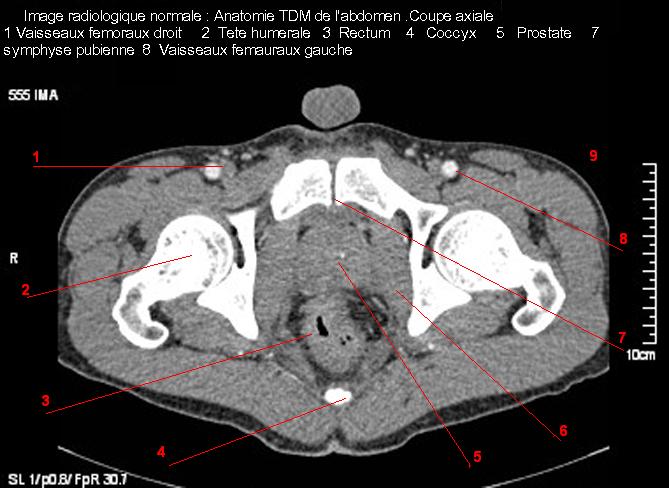

Images radiologique TDM normale de l'abdomen et tube digestif en coupe axiale ( CT scanner )  :

Coupe axiale     Coupe frontale      Coupe  sagitale